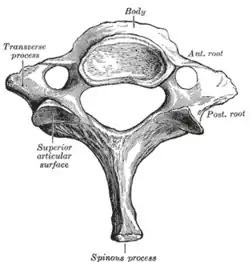

![]() A human cervical vertebra | |

By convention, the cervical vertebrae are numbered, with the first one (C1) closest to the skull and higher numbered vertebrae (C2–C7) proceeding away from the skull and down the spine. The general characteristics of the third through sixth cervical vertebrae are described here. The first, second, and seventh vertebrae are extraordinary, and are detailed later.

- The bodies of these four vertebrae are small, and broader from side to side than from front to back.

- The anterior and posterior surfaces are flattened and of equal depth; the former is placed on a lower level than the latter, and its inferior border is prolonged downward, so as to overlap the upper and forepart of the vertebra below.

- The upper surface is concave transversely, and presents a projecting lip on either side.

- The lower surface is concave from front to back, convex from side to side, and presents laterally shallow concavities that receive the corresponding projecting lips of the underlying vertebra.

- The pedicles are directed laterally and backward, and attach to the body midway between its upper and lower borders, so that the superior vertebral notch is as deep as the inferior, but it is, at the same time, narrower.

- The laminae are narrow and thinner above than below; the vertebral foramen is large and of a triangular form.

- The spinous process is short and bifid, the two divisions being often of unequal size. Because the spinous processes are so short, certain superficial muscles (the trapezius and splenius capitis) attach to the nuchal ligament rather than directly to the vertebrae; the nuchal ligament itself attaching to the spinous processes of C2–C7 and to the posterior tubercle of the atlas.

- The superior and inferior articular processes of cervical vertebrae have fused on either or both sides to form articular pillars, columns of bone that project laterally from the junction of the pedicle and lamina.

- The articular facets are flat and of an oval form:

- the superior face backward, upward, and slightly medially.

- the inferior face forward, downward, and slightly laterally.

- The transverse processes are each pierced by the foramen transversarium, which, in the upper six vertebrae, gives passage to the vertebral artery and vein, as well as a plexus of sympathetic nerves. Each process consists of an anterior and a posterior part. These two parts are joined, outside the foramen, by a bar of bone that exhibits a deep sulcus on its upper surface for the passage of the corresponding spinal nerve.